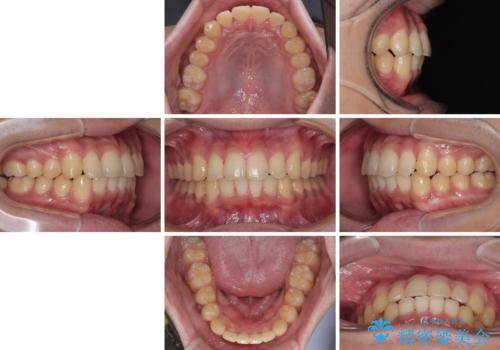

昼休みを活用して通院してくださり、1年半であっという間に終えることができました。

- 上下前歯の捻れやデコボコを気にして来院された患者様です。

口元はそれほど突出しておらず、患者様自身も気にしていらっしゃいませんでしたが、前歯の捻れやデコボコを解消すると、前方に拡大され、治療後に出っ歯仕上がりとなるリスクがあったため、補助装置により上顎臼歯を後方移動していくこととしました。